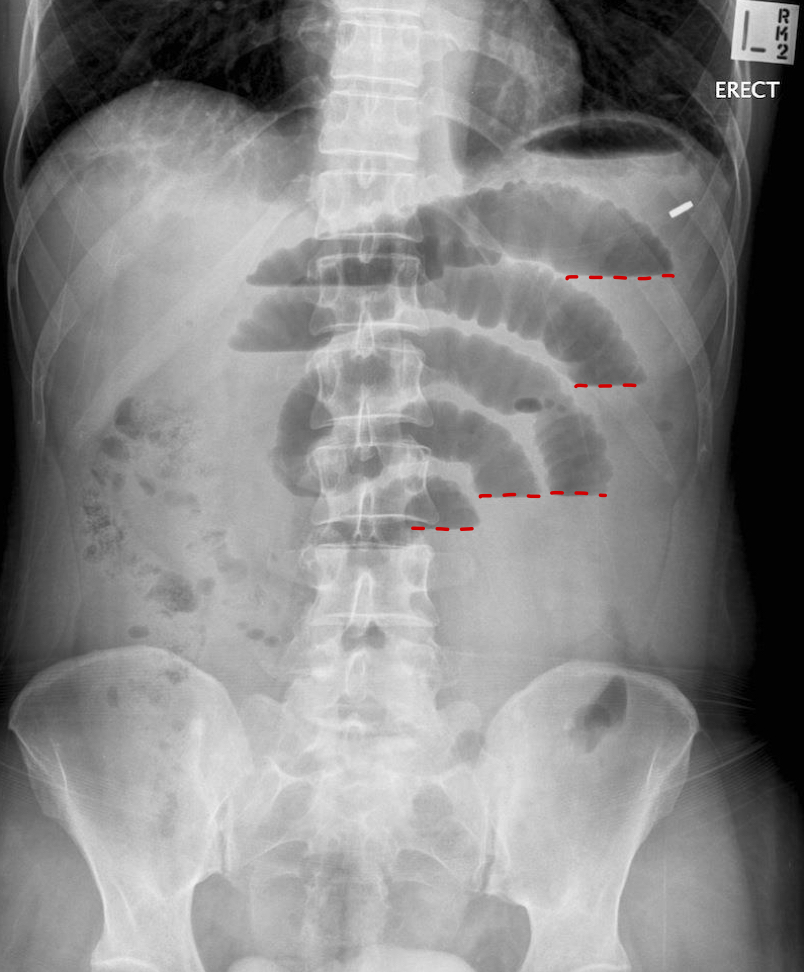

What is indicated by the shorter black arrows?

small bowel obstruction

What is indicated by the red dotted lines?